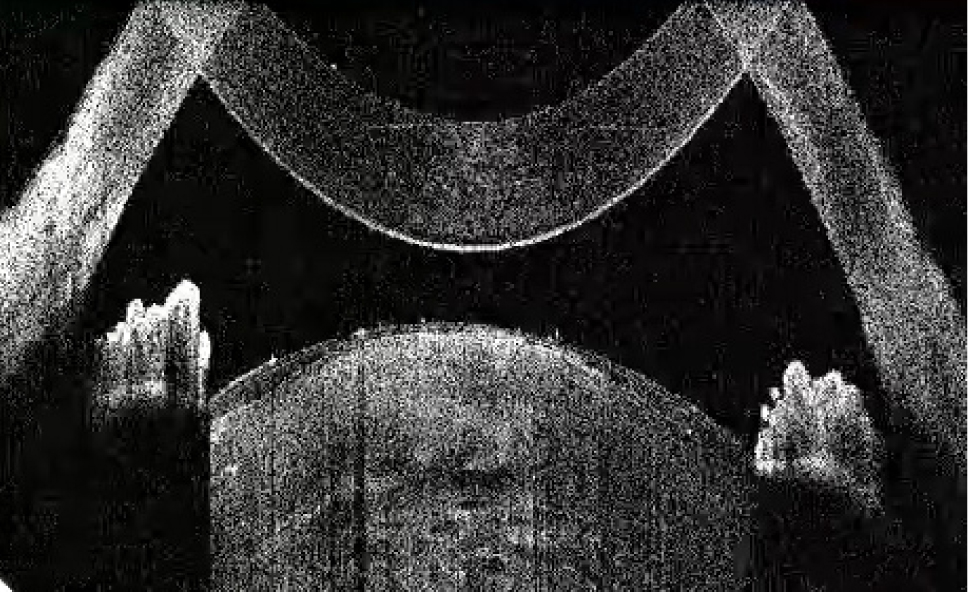

В исследование вошли 196 пациентов (250 глаз) с перезрелой катарактой. Пациенты были разделены на 2 группы (по 125 глаз в каждой группе). Всем пациентам интраоперационно с помощью интегрированной в операционный микроскоп И-ОКТ, Hi-R NEO (HAAG STREIT, Германия), определяли тип перезрелой катаракты (рис. 1–4).

Рис. 4. Тип 4 перезрелой катаракты: гомогенные передние кортикальные слои хрусталика вида «матового стекла»